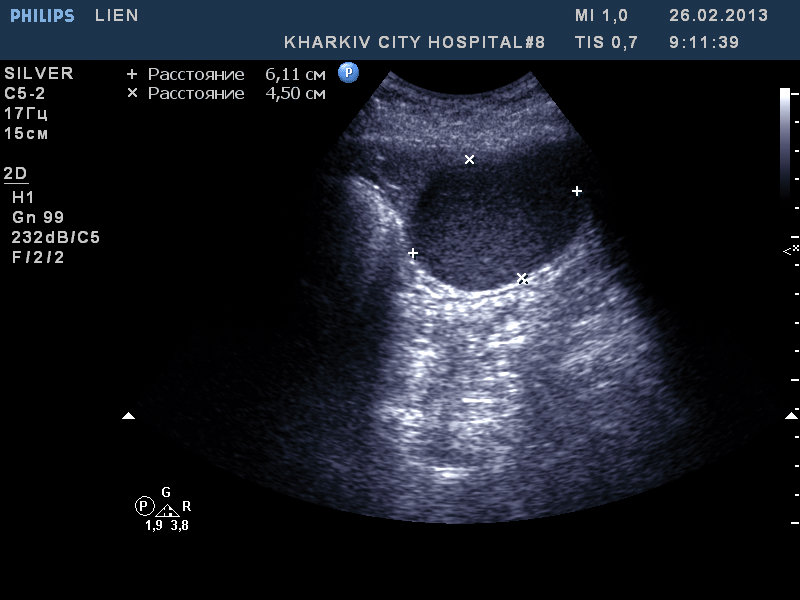

Удивительно, но факт - вчера к нам поступила такая-же "селезенка".

В нашем случае - это кистозное образование - при изменении положения тела происходит перемешивание жидкости внутри

В анамнезе у девушки была травма и перелом поясничного позвонка.

Re: образование селезенки

"Это становится интересным" © робот Вертер.

Рекомендовал КТ. Попробую узнать результат

Сегодня задренировал, содержимое - см. фото

Цитология: белковый преципитат, большое количество эритроцитов, лейкоцитов 5-8 в поле зрения.

Таким образом, видимо, в нашем случае это посттравматическая киста.